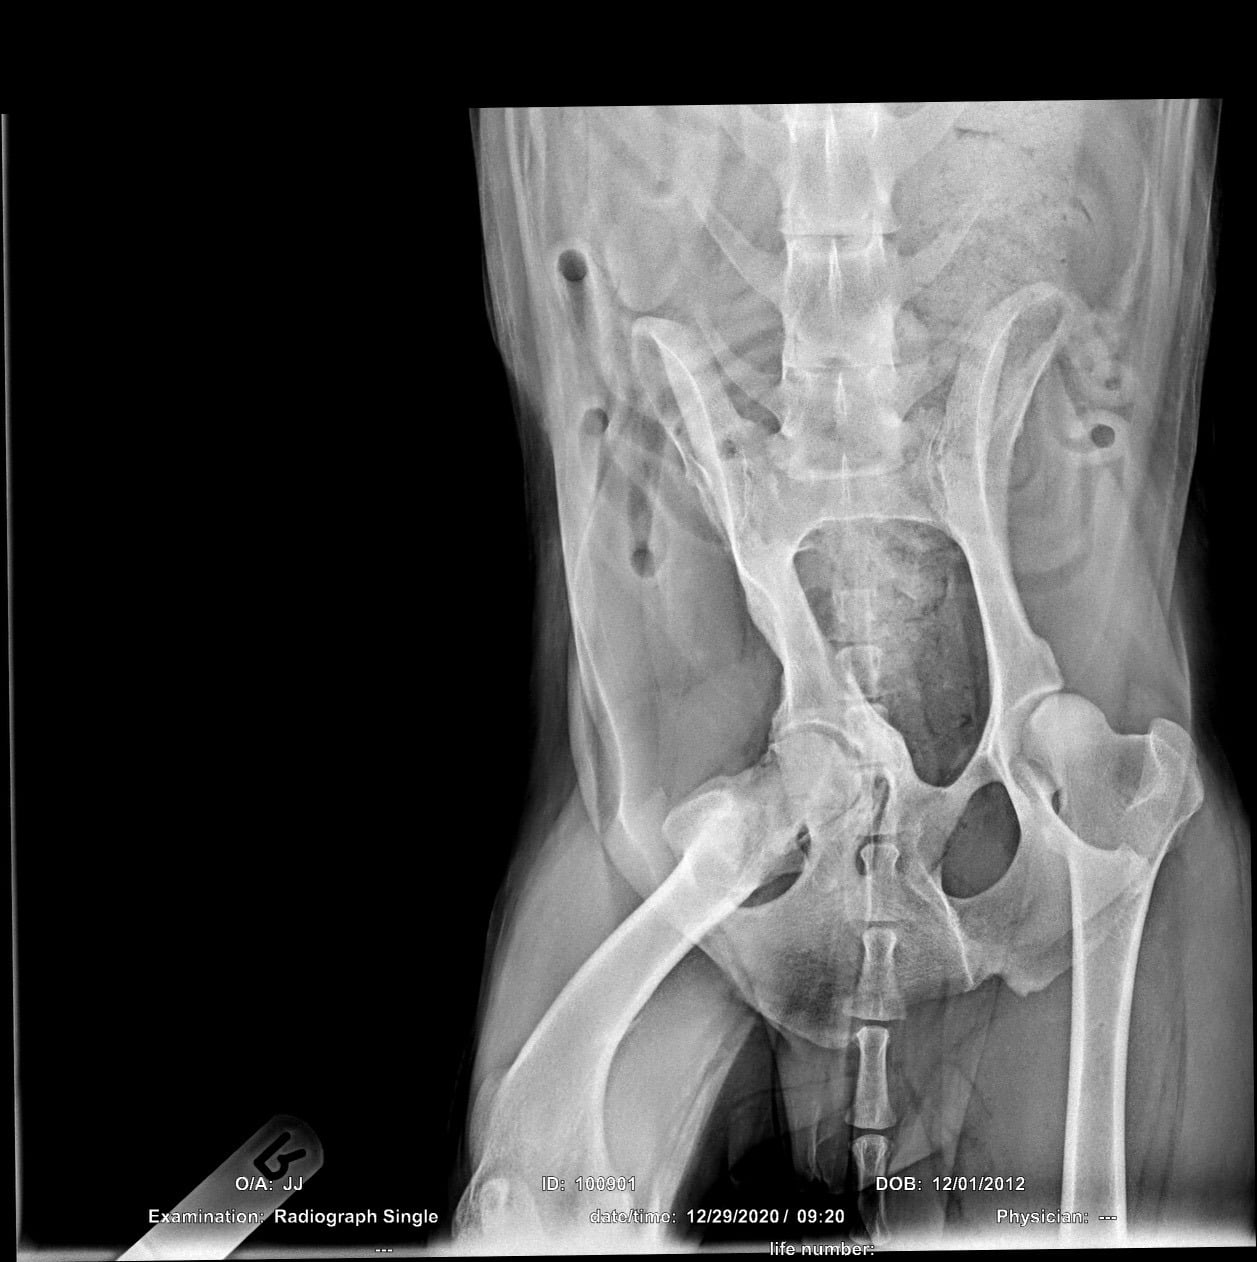

Here’s JJ. He came into rescue a month ago, straight away we noticed he was struggling with his hip and was given painkillers and an X-ray,. The result was he had been hit by a car many many years ago, he is 8 now. He went to a very talented Orthopaedic Vet, only option for pain relief for this lovely chap was a hip replacement. Here he is going with with his foster mum before op, and after. He will stay with his foster family, for recovery and rehab. We will be looking for a quiet home for him. He likes people dogs and cats, but more so men and food! We will be looking to raise funds for the costs, as we had to act quickly. So watch this space. I will update you as soon as we have further news as he is still in the vets. He’s such a lovely boy he’s worth every penny for a new chance pain free.